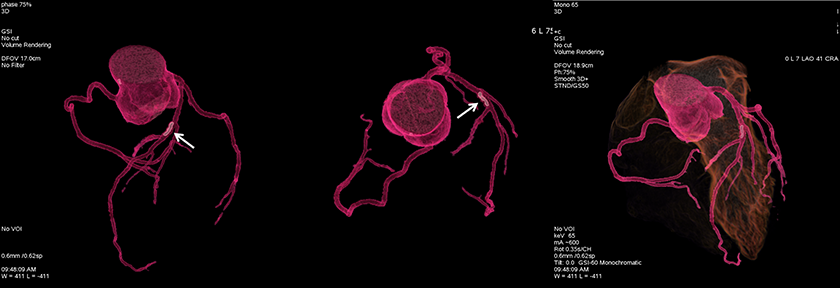

病例展示:Tree VR+透视图

左前降支(LAD)中段长条状硬化斑块(白色箭头)